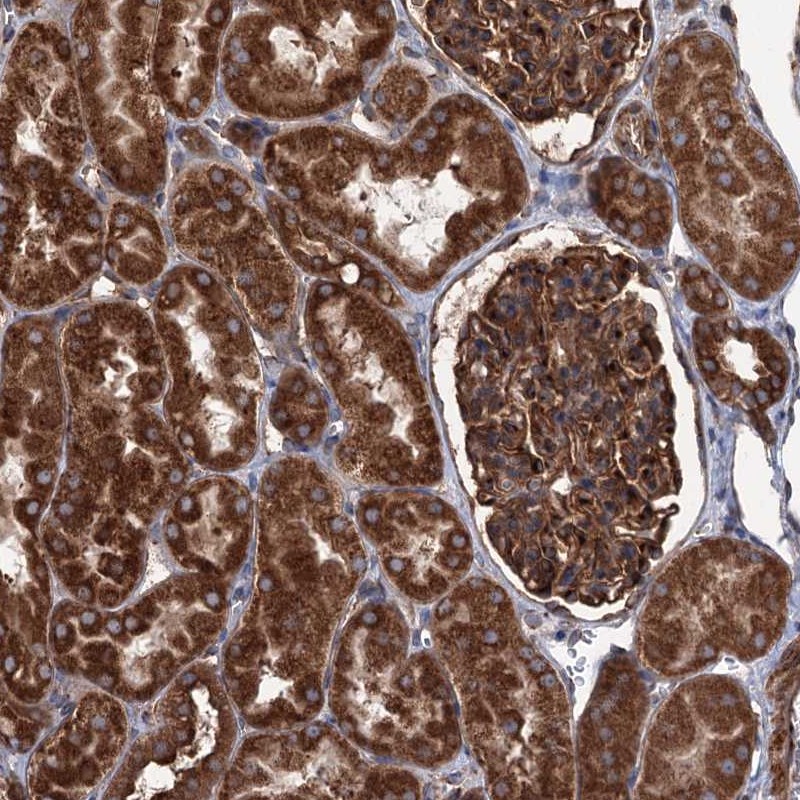

Immunohistochemical staining of human kidney shows strong cytoplasmic positivity in cells in tubules and cells in glomeruli.